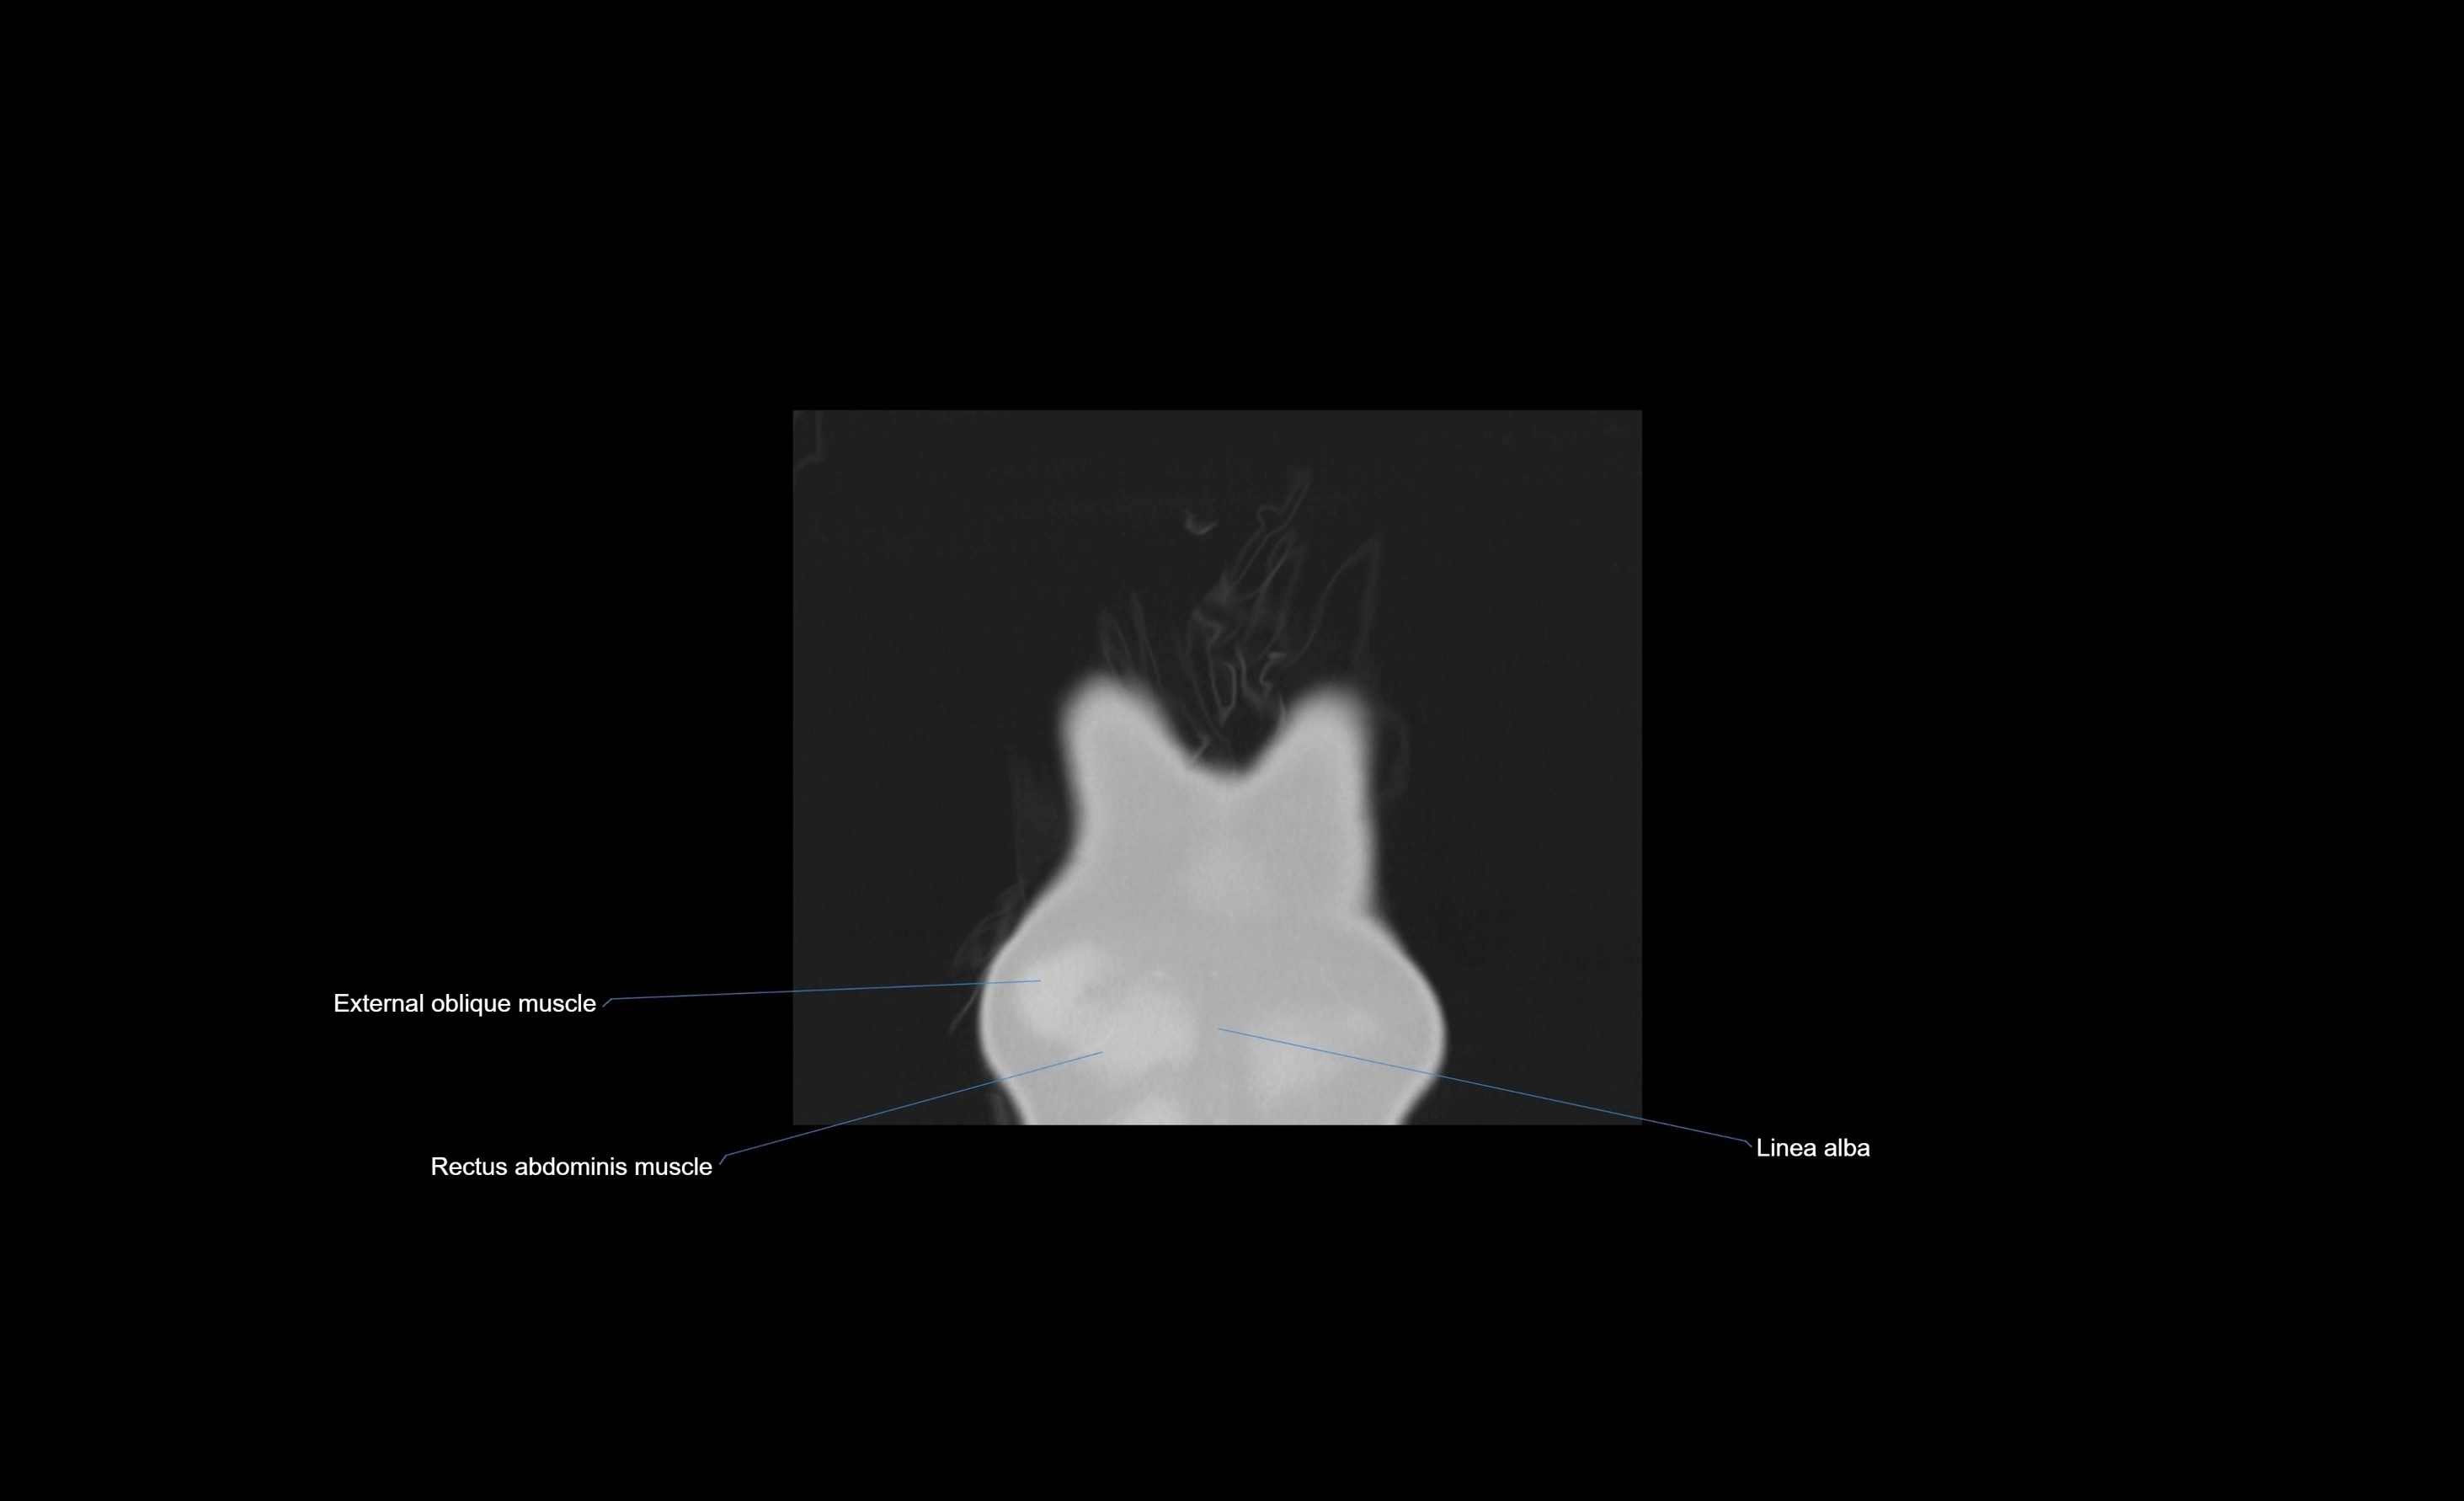

- External oblique muscle

- Rectus abdominis muscle